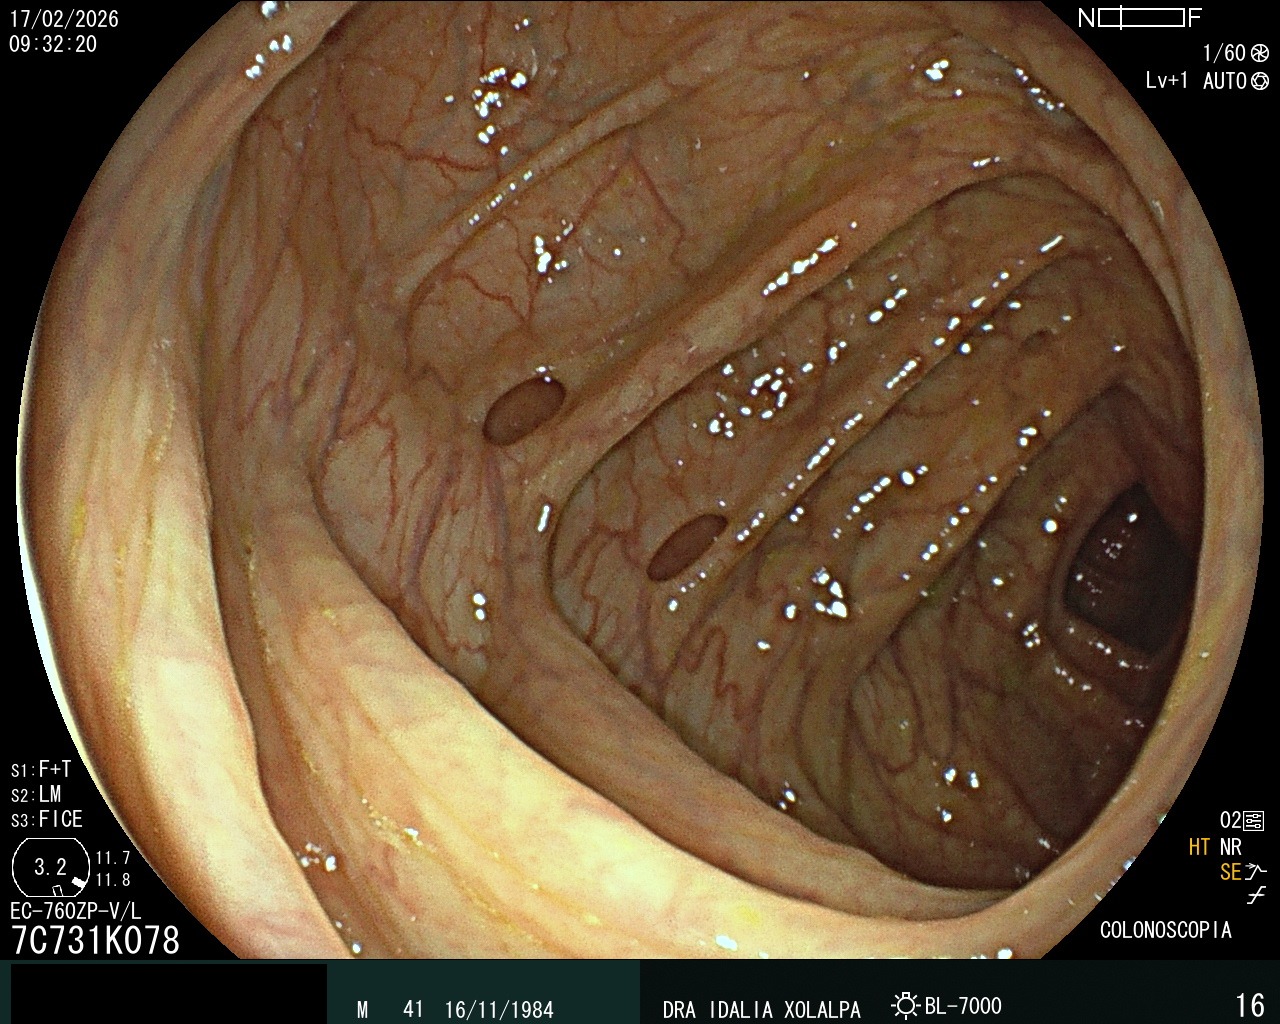

Divertículos